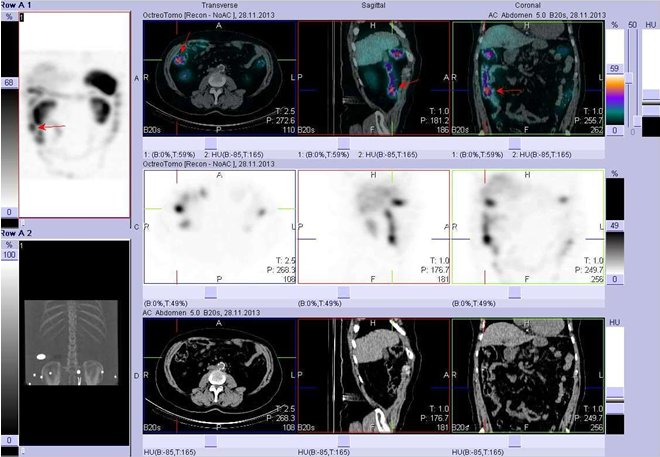

/  Obr. č. 2:   Fúze obrazů SPECT a CT. Vyšetření 4 hod. po aplikaci radiofarmaka. Vlevo zaměřeno na ložisko v pravé plíci parahilozně, vpravo zaměřeno na játra.

Vlevo i vpravo vždy nahoře SPECT, uprostřed CT, dole fúze obrazů. Vždy nad sebou: vlevo transverzální řezy, uprostřed sagitální řezy, vpravo koronární. /